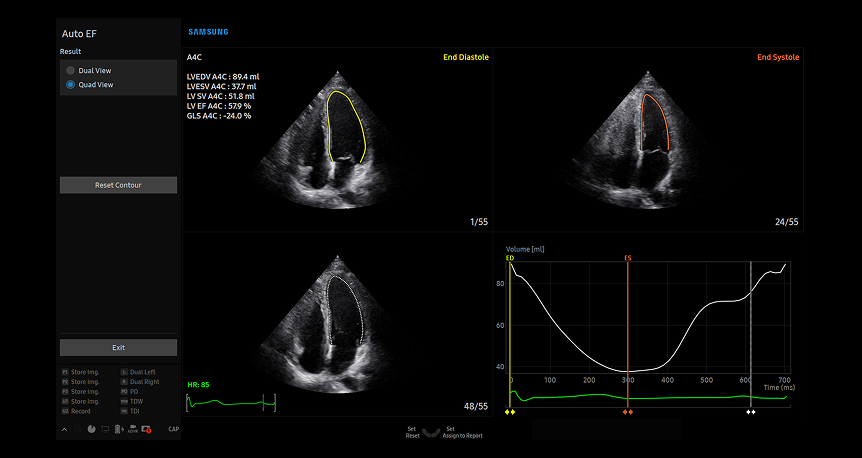

AutoEF

AutoEF cardiac assessment tool showing multi-view heart chamber visualization with automated ejection fraction measurements and volumetric analysis graph for quick diagnostic evaluation

AutoEF AutoEF è una funzione che misura e quantifica comodamente l'Eiezione e la Frazione, il volume del ventricolo sinistro e anche la deformazione longitudinale globale (GLS). Viene calcolato il punto endosistolico e quello endodiastolico del ventricolo sinistro, per facilitare una valutazione rapida ed efficiente del cuore.